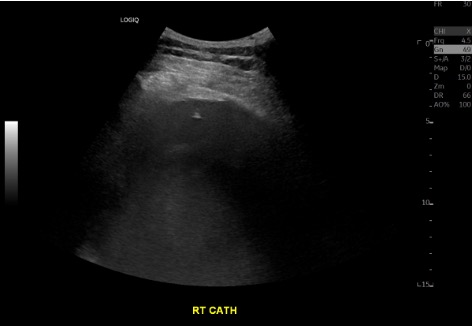

Catheter placement under US

Ultrasound during thoracentesis showing catheter in right pleural effusion